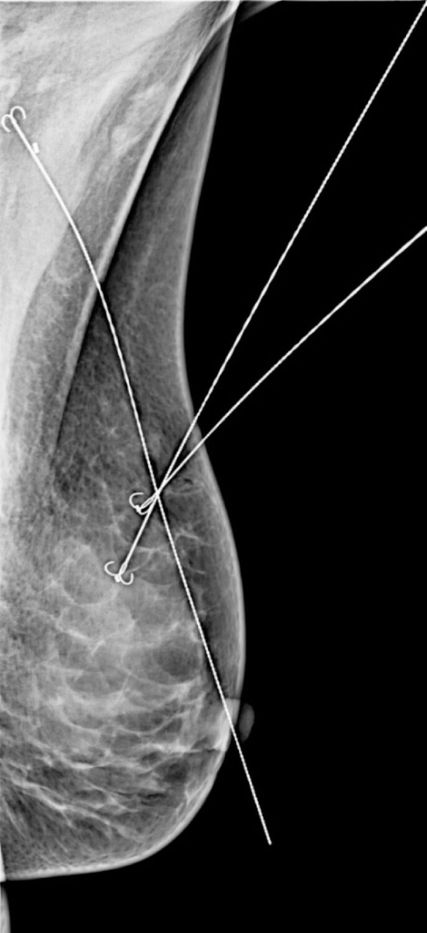

Goldstandard der Früherkennung sind nach wie vor die Mammografie und die Sonografie der Brust, in bestimmten Fällen wird als weiterführende Untersuchung eine MRT durchgeführt. Dies ist sinnvoll bei multiplen Herden, ausgedehntem Mikrokalk und unklarem Befund in der konventionellen Bildgebung. Es werden alle suspekten Läsionen biopsiert und auch klippmarkiert, um nach einer eventuellen neoadjuvanten Therapie die ehemals betroffenen Areale lokalisieren zu können. Suspekte Lymphknoten werden zunehmend auch biopsiert und markiert, um bei gutem Ansprechen auf eine neoadjuvante Therapie auch die Chirurgie der Axilla reduzieren zu können.

Prinzipiell sollte immer eine brusterhaltende Resektion angestrebt werden. Auch bei multiplen Herden ist das oft durch sorgfältige Markierung aller suspekten und biopsierten Läsionen möglich. Bei ausgedehnten Resektionen kann durch Parenchymadaptationen bzw. -rotationen und onkoplastische Techniken ein gutes kosmetisches Ergebnis erzielt werden. Durch perimamilläre Schnittführung und schonenden Umgang mit dem Gewebe sind Narben oft schon nach kurzer Zeit kaum noch sichtbar.